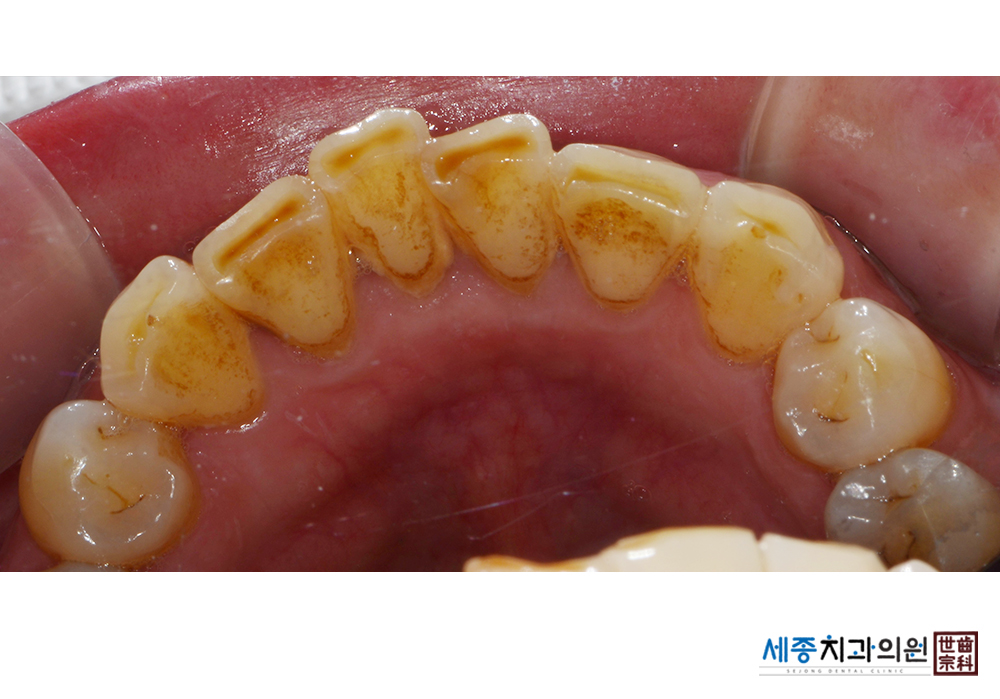

[스케일링] 치주질환 예방 스케일링

치료전 : 2021-03-02

치료후 : 2021-03-02

가글마취&저주파 스켈러를 사용한 스케일링